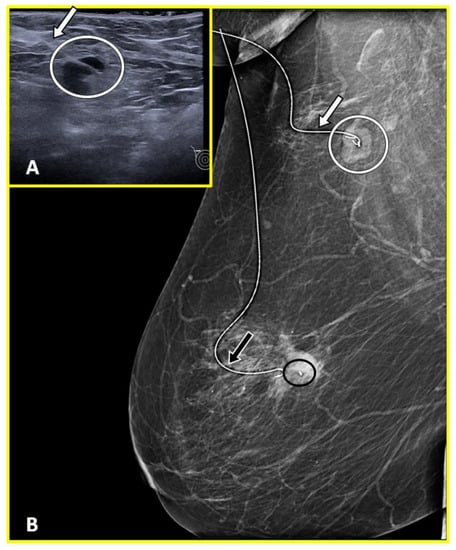

2.6.1. Radioactive Seed Localization